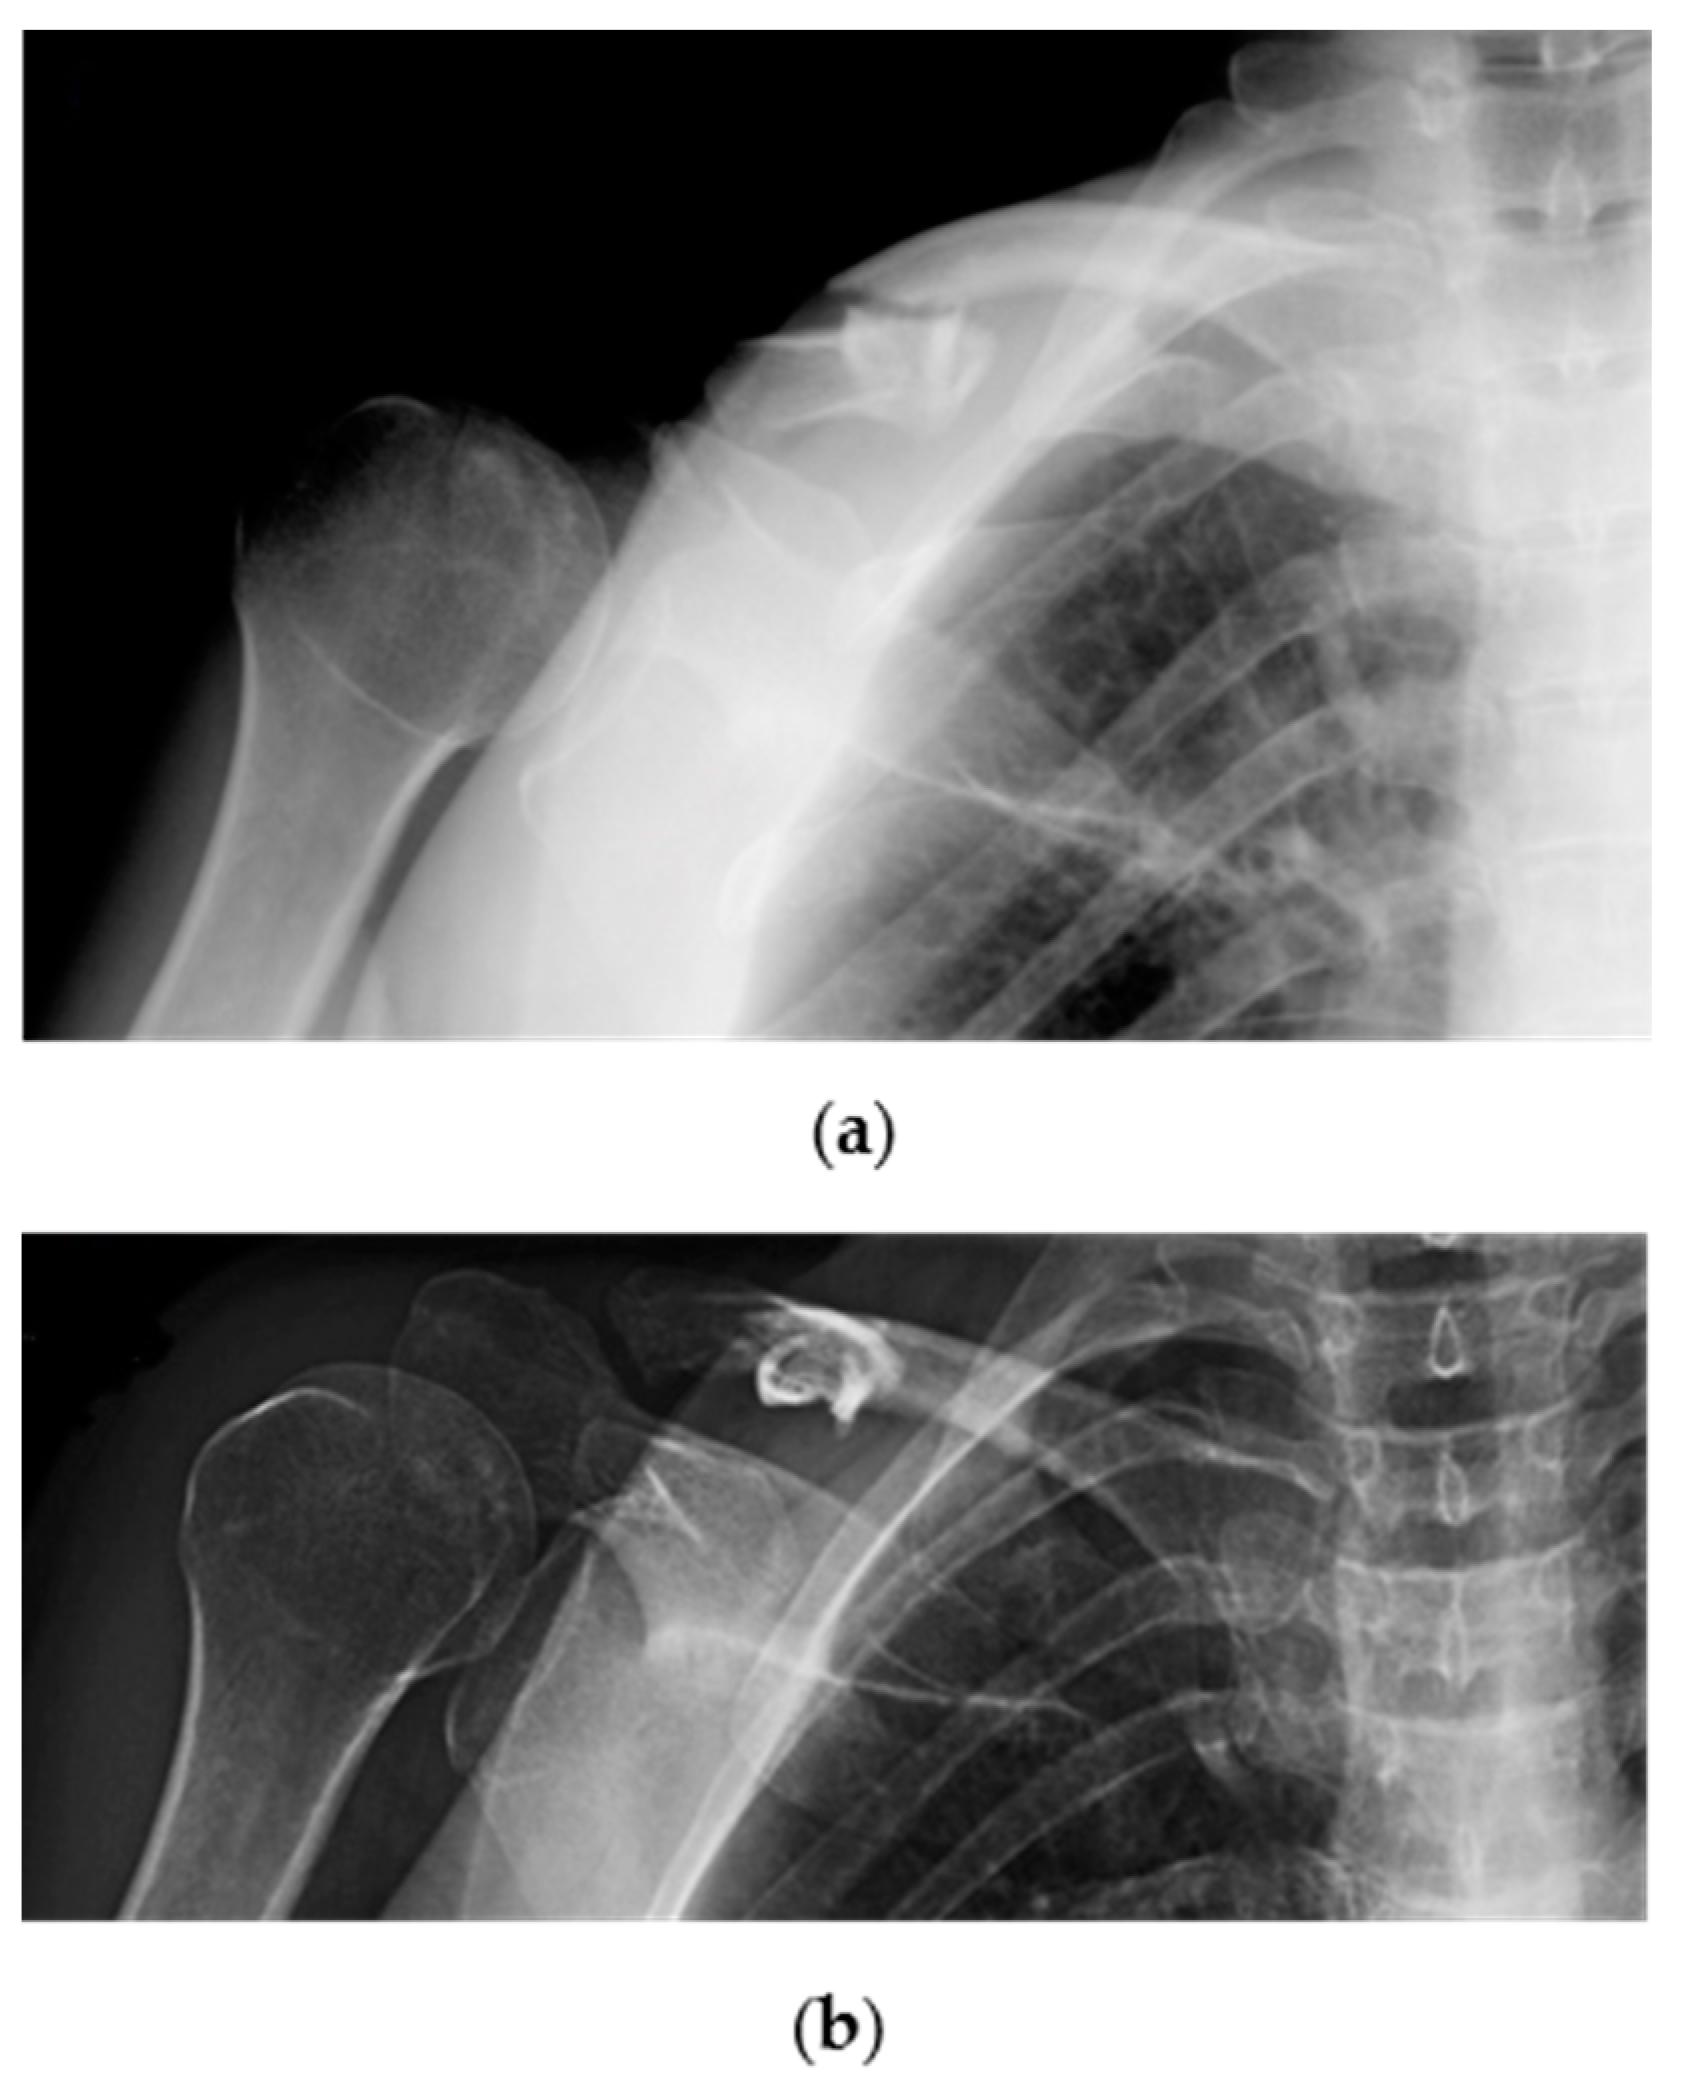

- Tagliapietra, J.; Belluzzi, E.; Biz, C.; Angelini, A.; Fantoni, I.; Scioni, M.; Bolzan, M.; Berizzi, A.; Ruggieri, P. Midshaft Clavicle Fractures Treated Nonoperatively Using Figure-of-Eight Bandage: Are Fracture Type, Shortening, and Displacement Radiographic Predictors of Failure? Diagnostics 2020, 10, 788. [Google Scholar] [CrossRef]